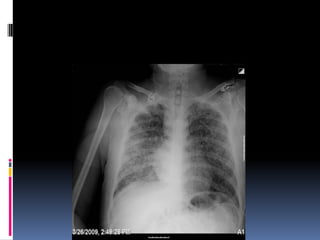

Penetration / Exposure

 Able to see ribs

through the heart

 Barely see the

spine through the

heart

 Pulmonary vessels

can be traced

nearly to the edges

of the lungs

Penetration / Exposure Able to see ribs through the heart  Barely see the spine through the heart  Pulmonary vessels can be traced nearly to the edges of the lungs